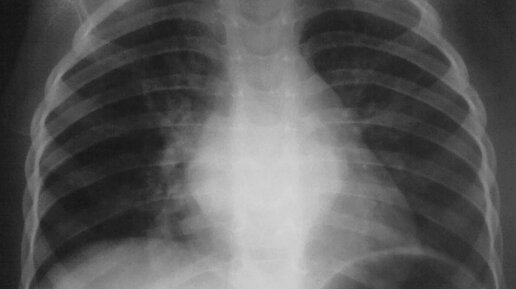

Бронхит — воспаление бронхов, органов дыхательной системы, по которым воздух попадает в легкие. Это довольно распространенная болезнь (ежегодно болеет около 5-10% людей), поэтому стоит понимать причины, симптомы и основные принципы лечения. Рассказываем главное с помощью врача-терапевта Кутузовского центра Evolutis clinic Юлией Буцких. Разновидности бронхита Воспалительный процесс в бронхах может быть: Кроме классификации по длительности болезни различают другие виды бронхита: Причины бронхита Чаще всего острый бронхит вызывается: Основная причина хронического бронхита — курение...

Бронхи (от др.-греч. βρόγχος — «дыхательное горло, трахея» лат. bronchia) — ветви дыхательного горла у высших позвоночных (амниот) (в том числе человека). Бронхи составляют воздухоносные пути, в них не идёт газообмен (так называемое анатомическое мёртвое пространство). Их функция заключается в проведении воздушного потока в респираторные отделы (ацинусы), его согревании, увлажнении и очищении. Дыхательное горло, или трахея, у большинства животных делится на два главных бронха. Лишь у гаттерии продольная...